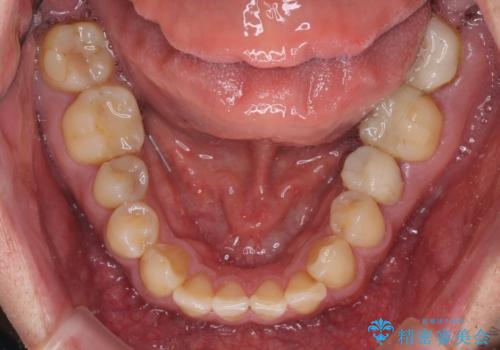

- 虫歯が多く、セラミッククラウンにより虫歯治療を行っている途中で矯正治療をしたいとのことで来院された患者様です。

上顎前歯が舌側に転位しており、なるべく早く楽に矯正したいとのことで、ワイヤー矯正を行うこととしました。

虫歯治療途中の歯は仮歯が装着されていたため、そのまま矯正治療を行い、矯正後に補綴治療を行うこととしました。